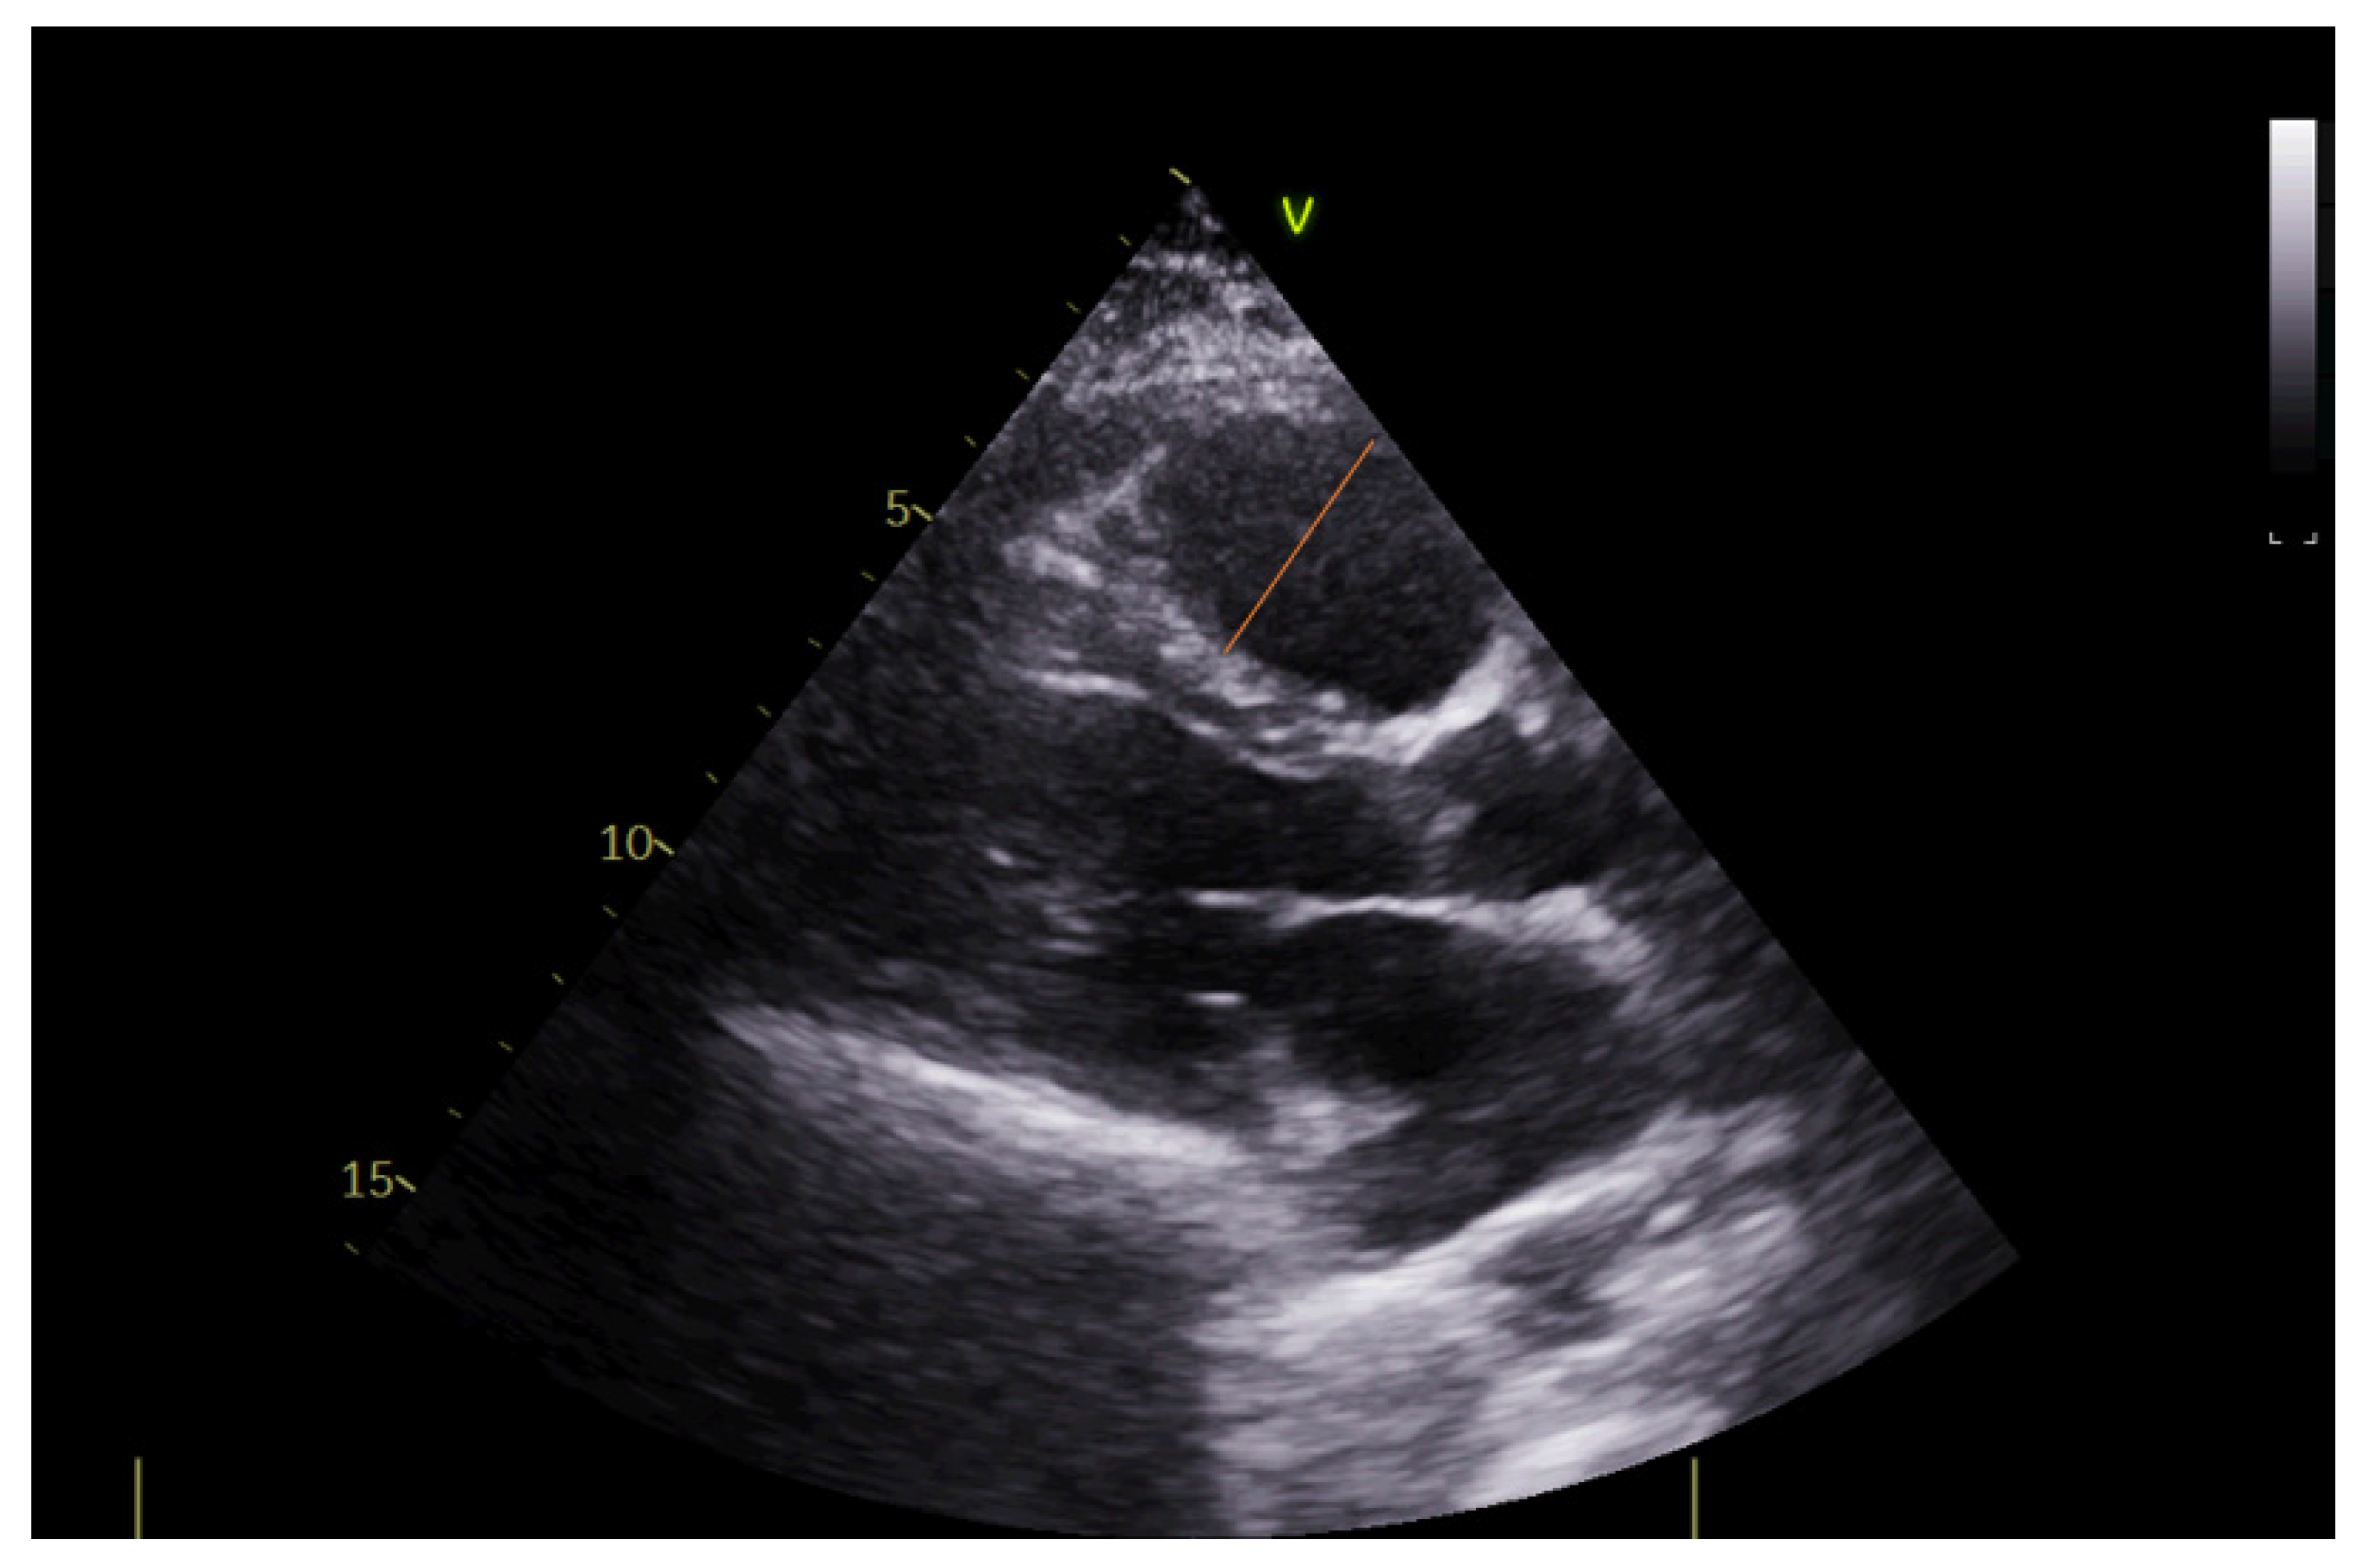

2.4. Echocardiography

| LV ejection fraction (%), mean ± sd | 57 ± 10 |

| Right ventricular diameter (mm), mean ± sd | 29 ± 6 |

| Right/left ventricular diameter ratio, mean ± sd | 0.64 ± 0.11 |

| Right atrial area (cm2), mean ± sd | 17.3 ± 5.3 |

| TAPSE (mm), mean ± sd | 23 ± 4 |

| S’RV (cm/s), mean ± sd | 16 ± 3 |

| PVAT (msec), mean ± sd | 120 ± 25 |

| RV ESP (mmHg), mean ± sd | 36 ± 11 |

| VCI (mm), mean ± sd | 15 ± 2 |

| Signs of deep vein thrombosis on color Doppler, yes, n (%) | 9 (28.1) |